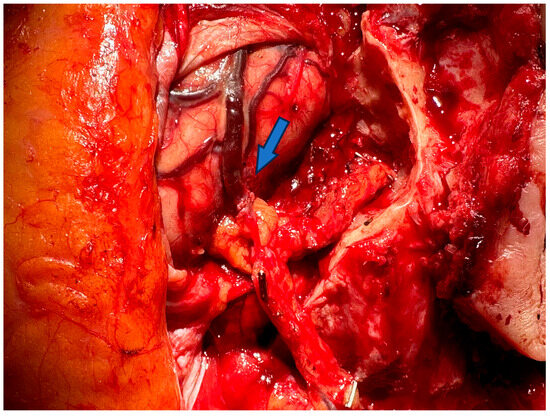

3.2. Advances of Nerve Bridging and Transfer